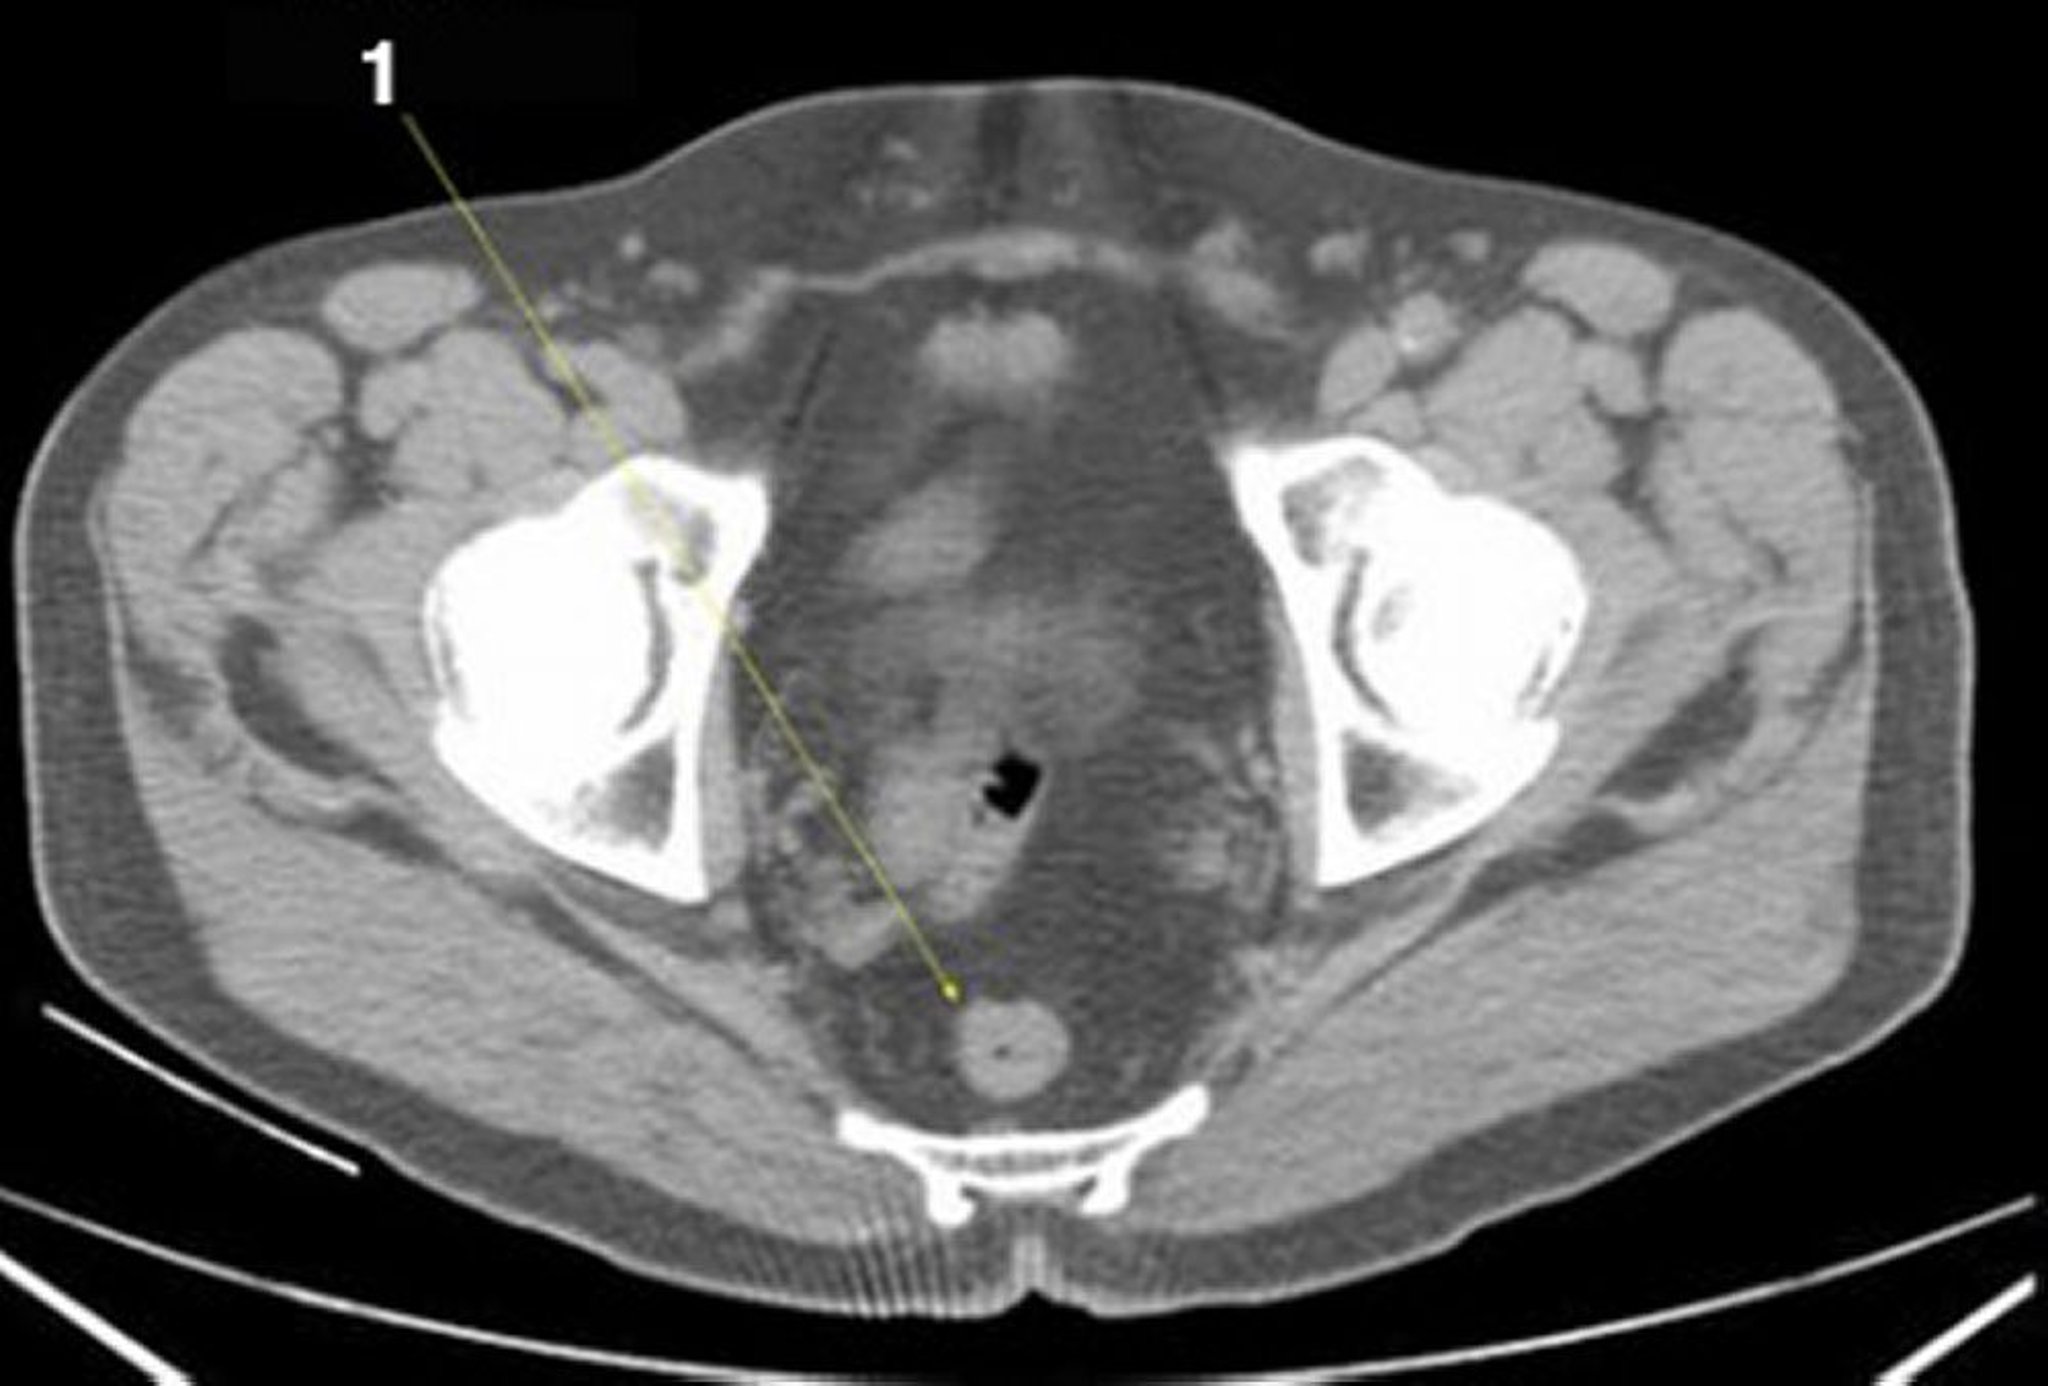

正常解剖を示した腹部および骨盤の単純CT画像(スライド27)

1 = 直腸。